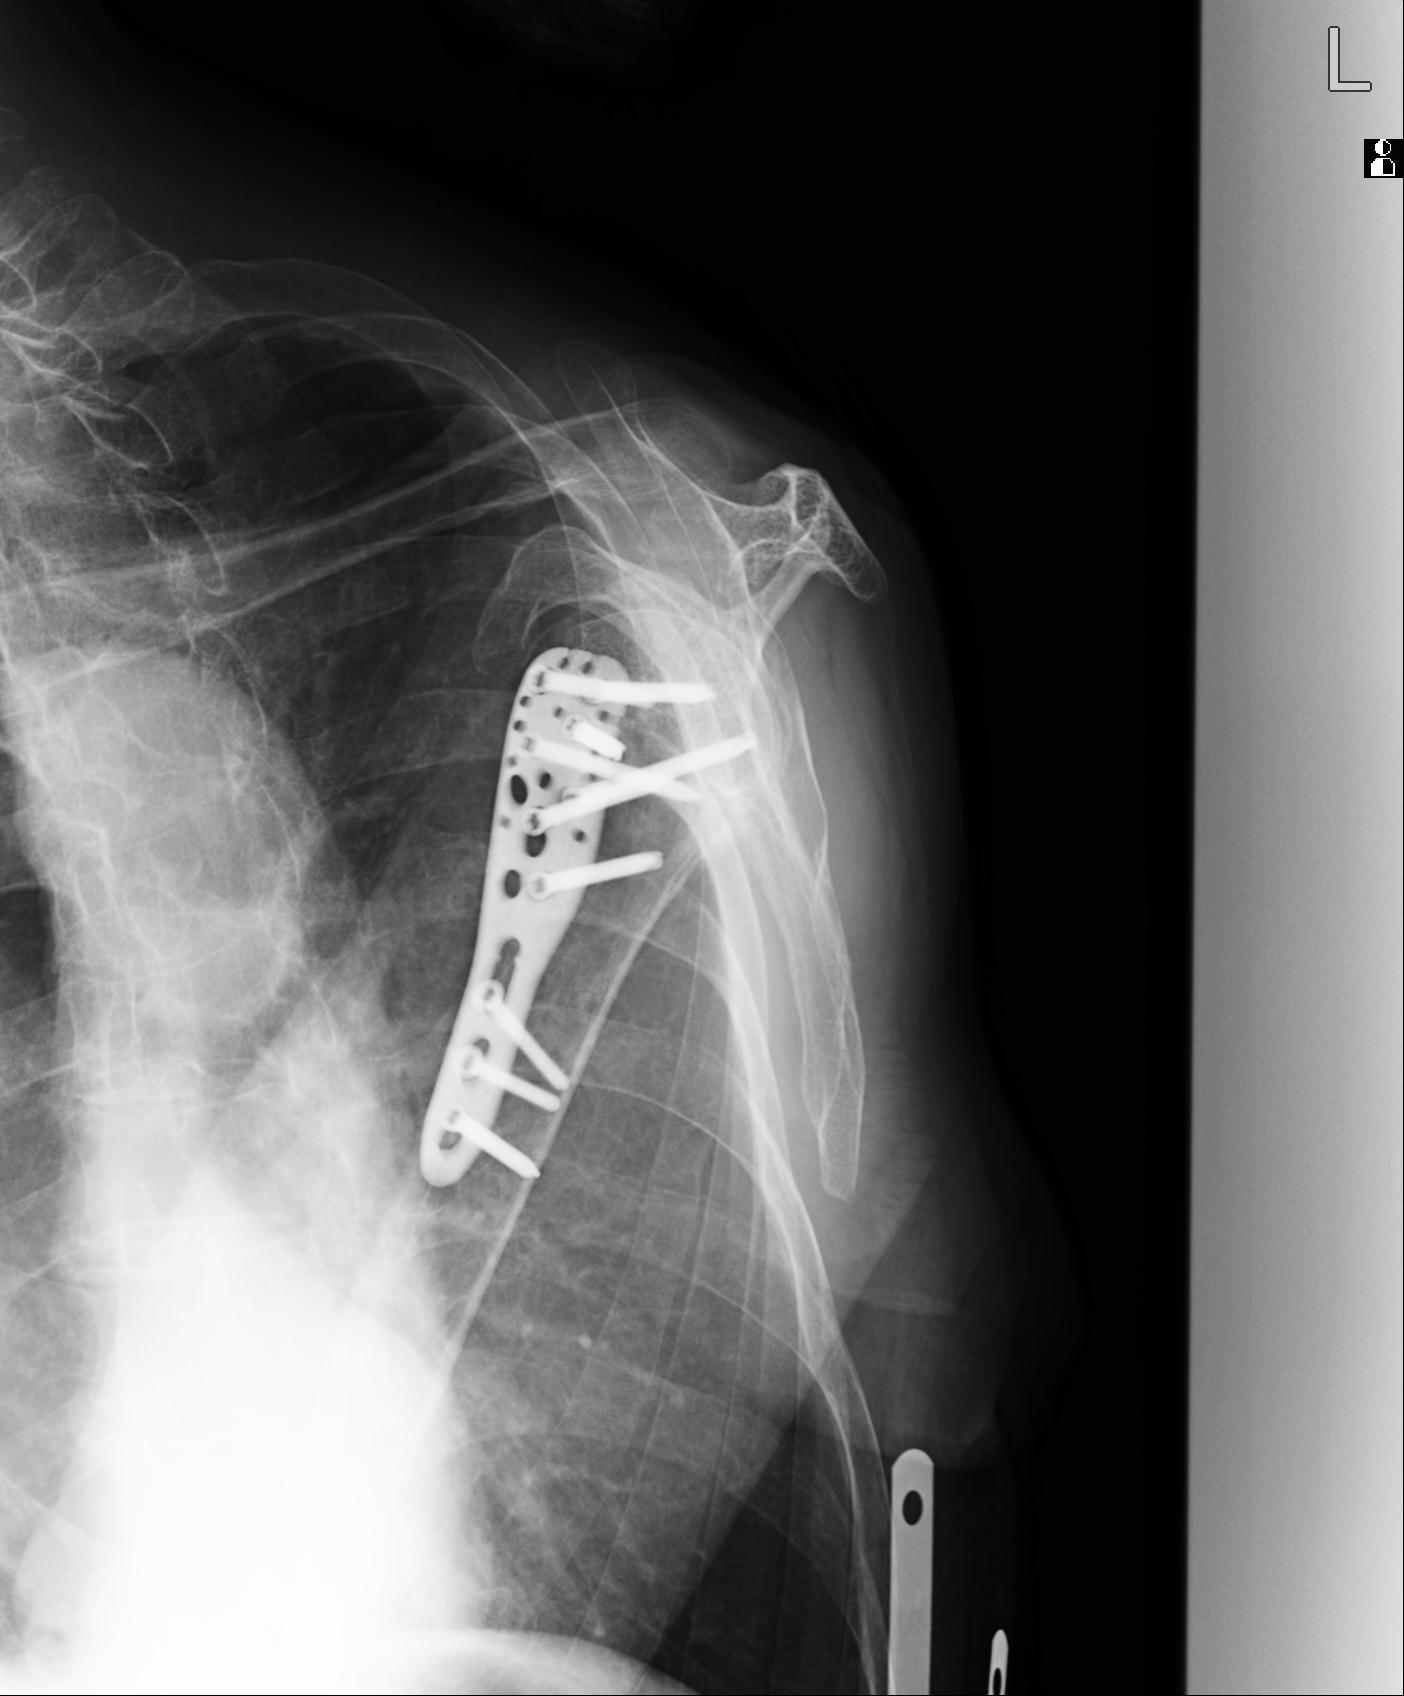

110214 12/20 肩 2R 12/21 肩 4R 72歳女性 左上腕外科頚プレート